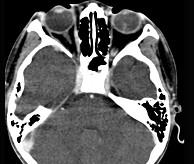

问题 女性,46岁,自述左眼视物不清约3个月,CT扫描如图所示,请选择正确的描述或答案 ( )

选项 A、考虑视网膜脱离 B、考虑玻璃体内出血 C、左侧玻璃体内偏后方见絮状高密度影 D、双侧眼环形态密度正常 E、双侧眼球未见病变

答案 C